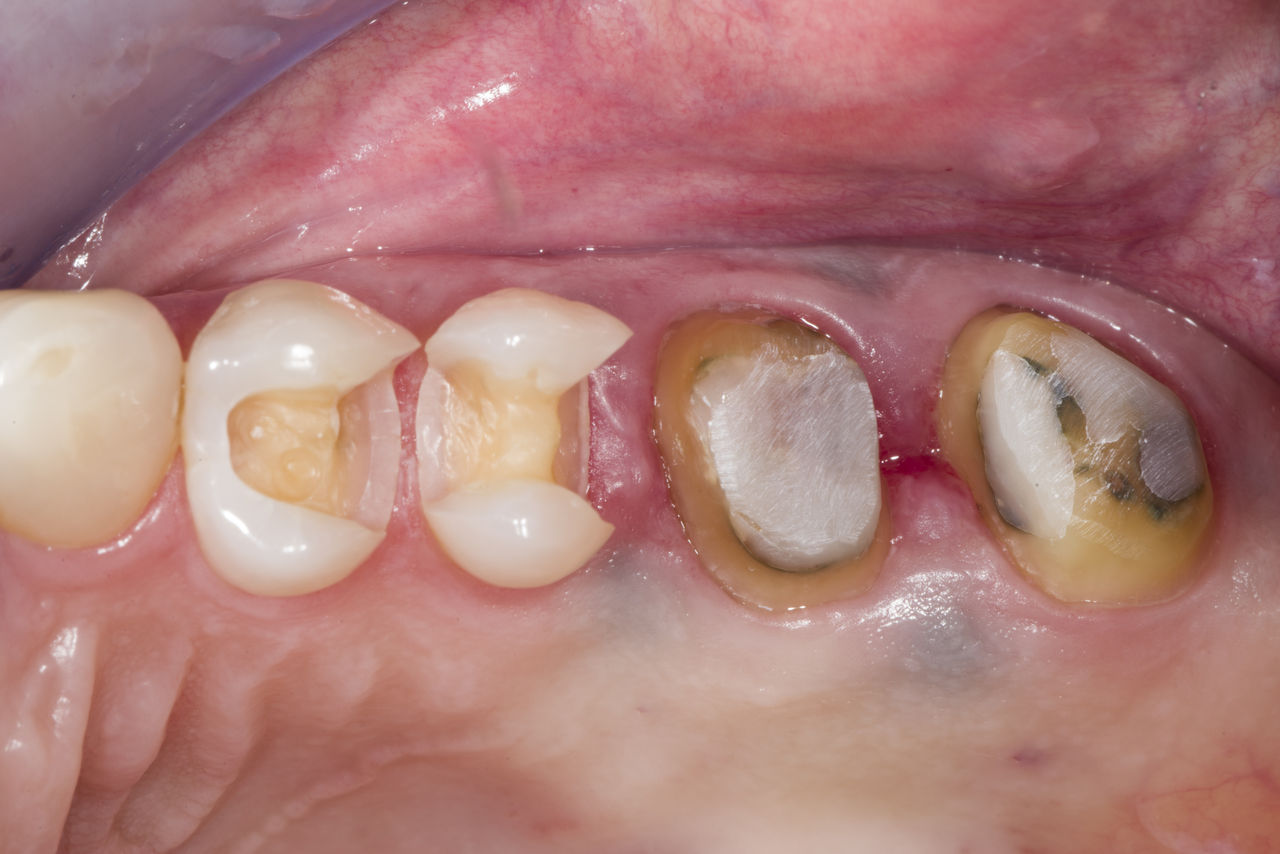

Lower second molar chairside restoration

A partial CEREC Tessera crown

A lower second molar with sensitivity presented with cracks as well as an extensive Class I composite restoration on the buccal surface. According to the minimally invasive concept a CAD/CAM partial crown was planned, fabricated and bonded using CEREC Tessera in a single visit.

Before: Failed amalgam restoration needing replacement. Patient complaining of sensitivity and tooth presenting multiple cracks.

After: Chairside CAD/CAM partial crown restoration fabricated with CEREC Tessera Advanced Lithium-Disilicate glass ceramic.

Dr. Carlos Eduardo Sabrosa

Rio de Janeiro, Brasil